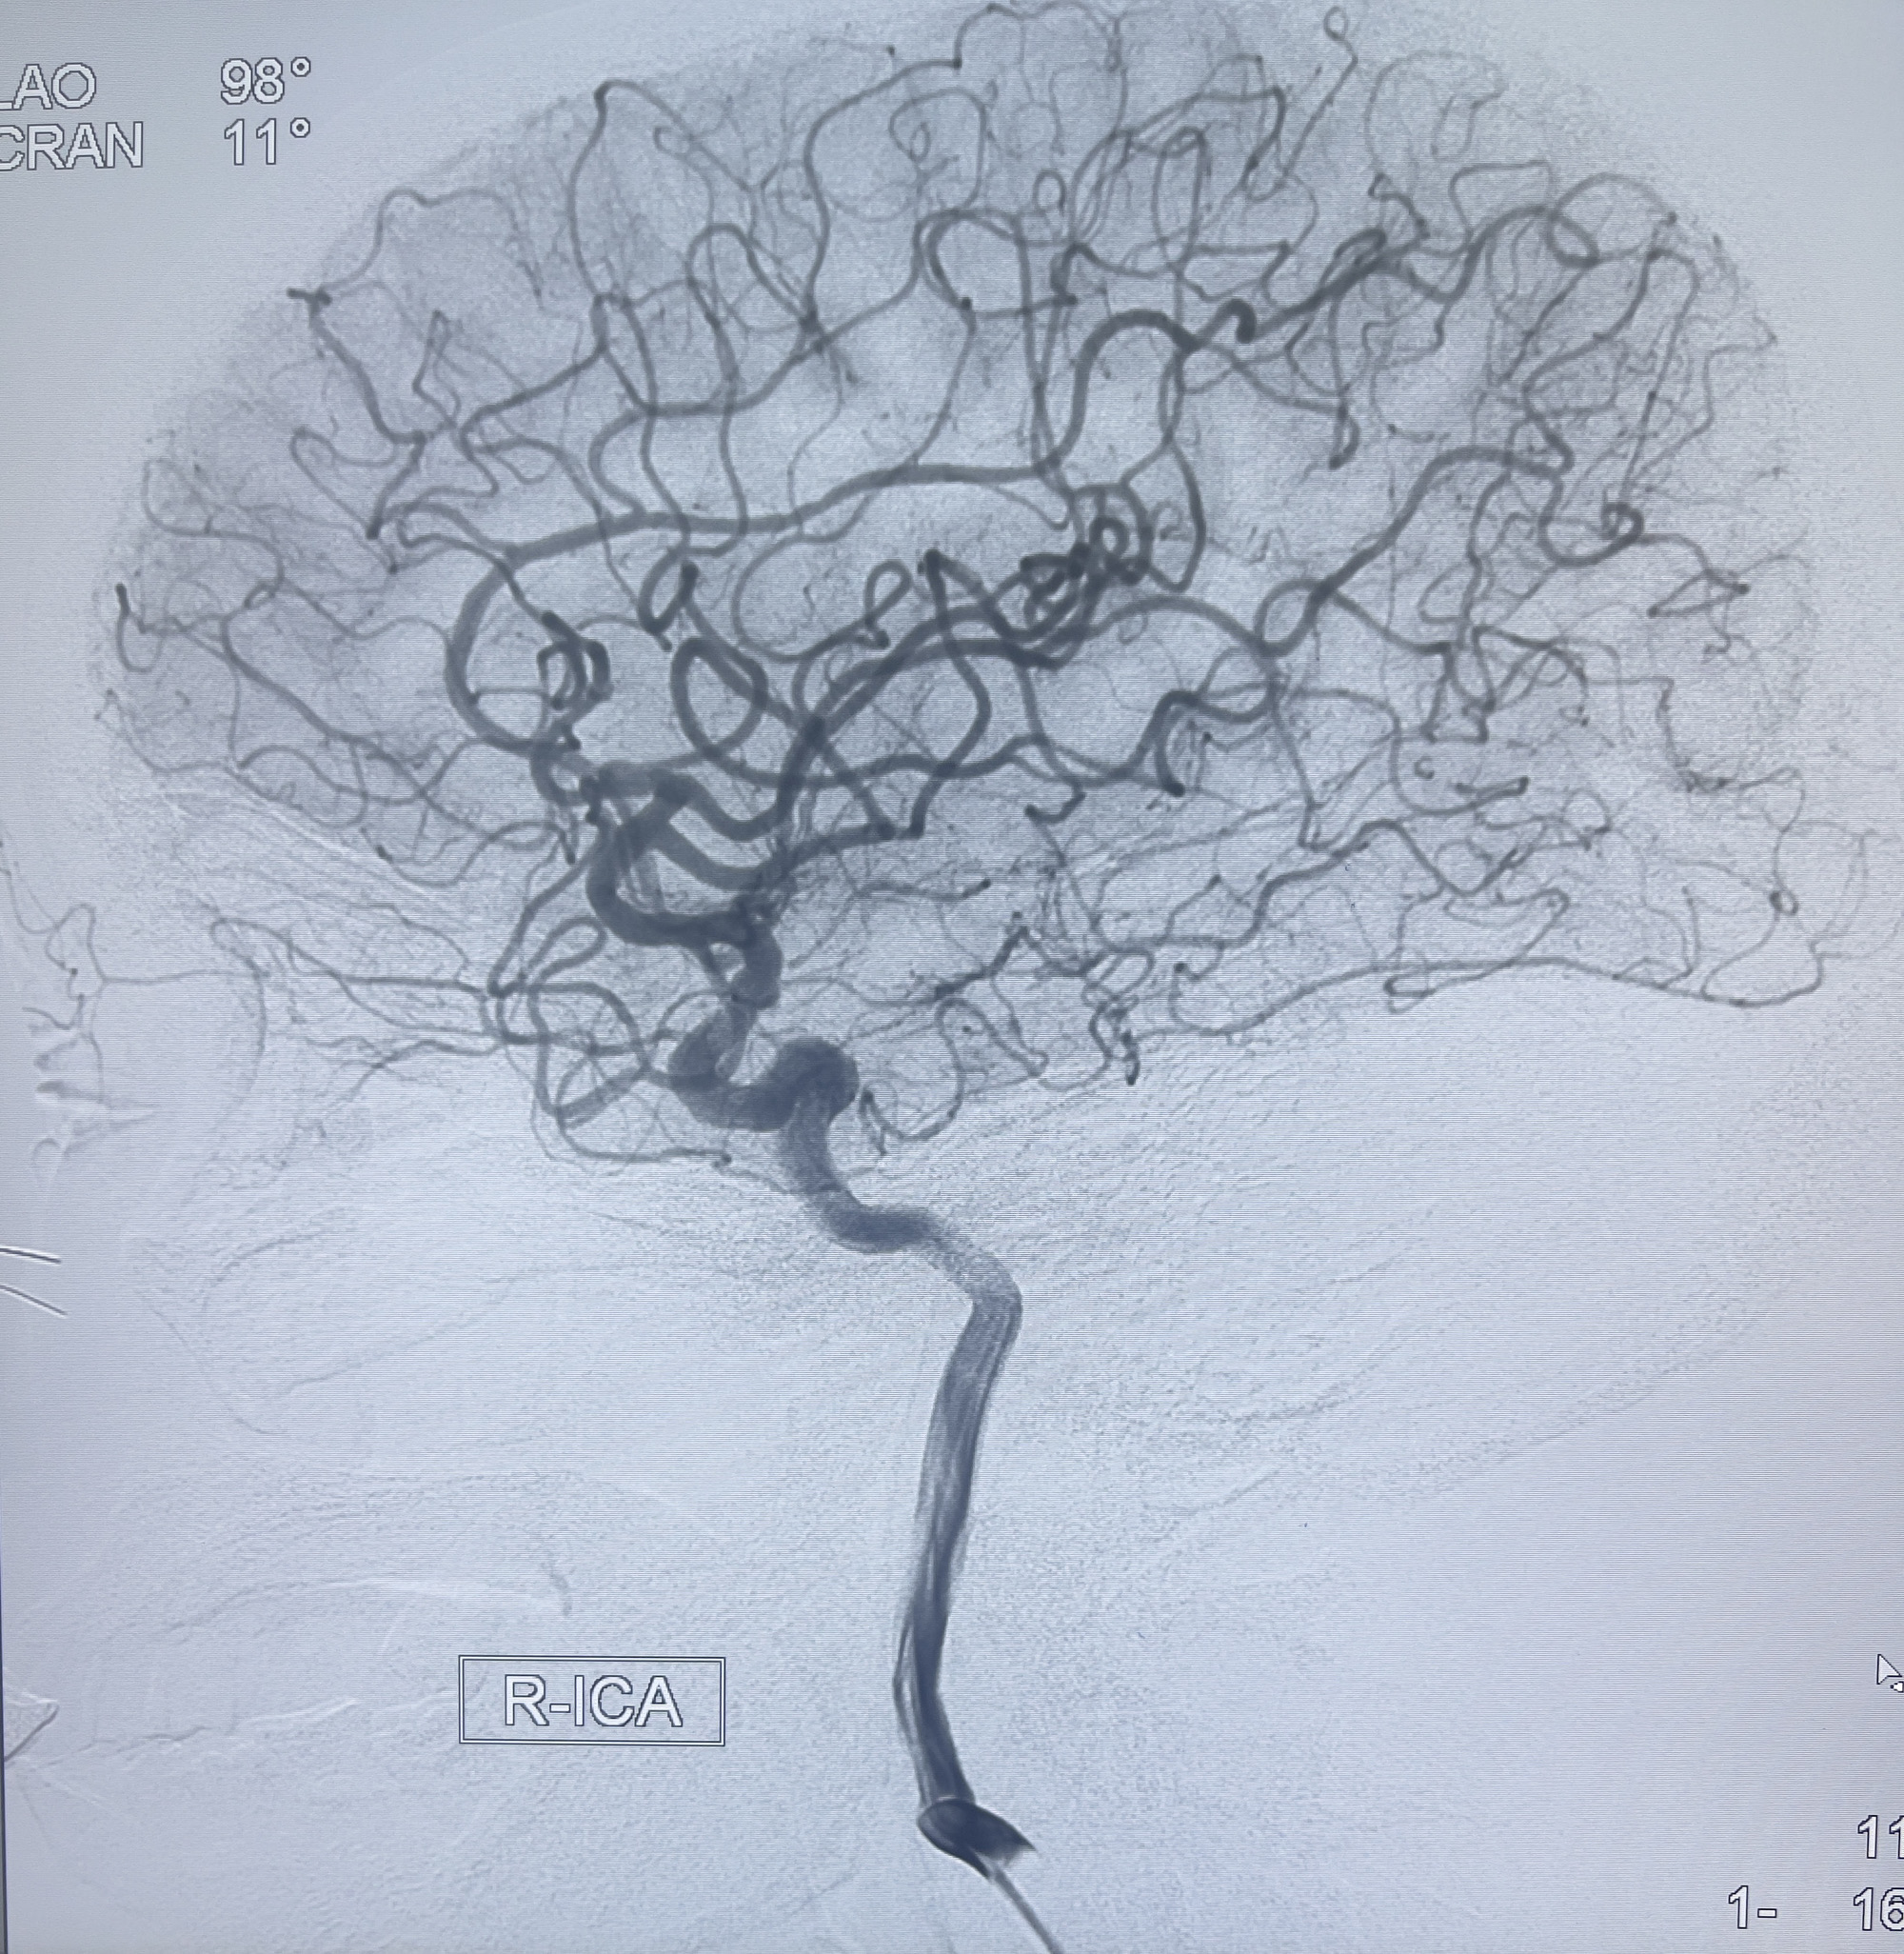

202.04.28脑血管造影:右侧大脑后动脉远段闭塞,右侧椎动脉V4段可见“囊状造影剂填充影”,大小7.64*7.65mm,可见PICA由动脉瘤发出;